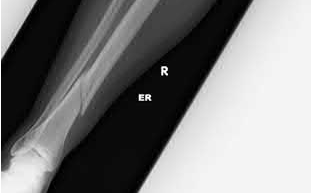

What is the most common type of malalignment after intramedullary nailing of distal 1/3 extra-articular tibia fractures using a infrapatellar approach when compared with plating?

The most common type of malalignment after intramedullary nailing of distal 1/3 extra-articular tibia fractures using an infrapatellar approach when compared with plating is valgus malalignment.

Fixation of distal one-third tibial shaft fractures can be successfully treated with either intramedullary nailing or plating. The literature describes advantages and disadvantages to both approaches, however intramedullary nailing has been shown to lead to increased rates of valgus malunion. Recent studies have shown that using a suprapatellar approach may decrease the incidence of valgus malalignement.

Primary angular malalignment was identified in 17 patients (16.3%). This included four patients treated with tibial plating (8.3%) and 13 patients treated with nails (23%, P = 0.02). Eight of these (7.7% of all patients) had malalignment between 6° and 10° of angulation. Valgus was the most common

angular deformity, accounting for 70% of angular deformity cases.